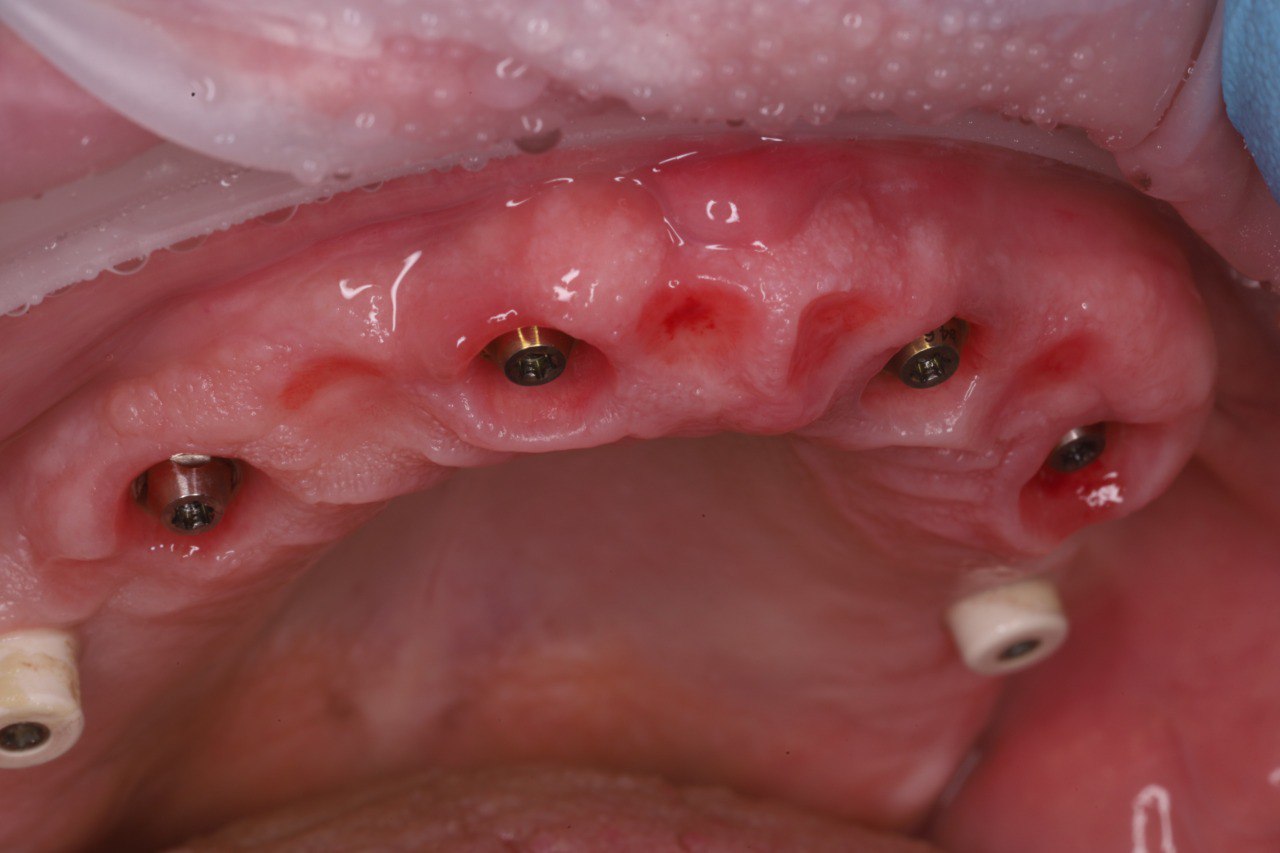

Имплантация зубов All-on-6